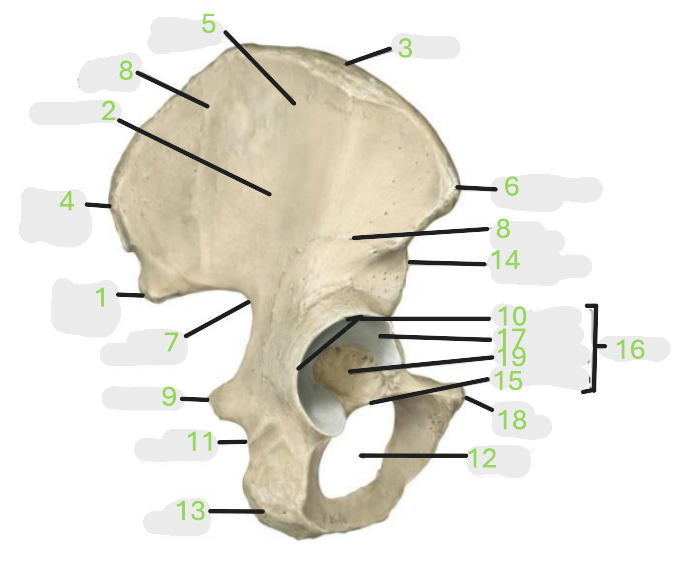

Where is the posterior inferior iliac spine

1

Where is the gluteal surface

2

Where is the iliac crest

3

Where is the posterior superior iliac spine

4

Where is the anterior gluteal line

5

Where is the anterior superior iliac spine

6

Where is the greater sciatic notch

7

Where is the inferior gluteal line

8

Where is the ischial spine

9

Where is the acetabular rim

10

Where is the lesser sciatic notch

11

Where is the obturator foramen

12

Where is the ischial tuberosity

13

Where is the anterior inferior iliac spine

14

Where is the acetabular notch

15

Where is the acetabulum

16

Where is the lunate surface

17

Where is the pubic tubercle

18

Where is the acetabular fossa

19